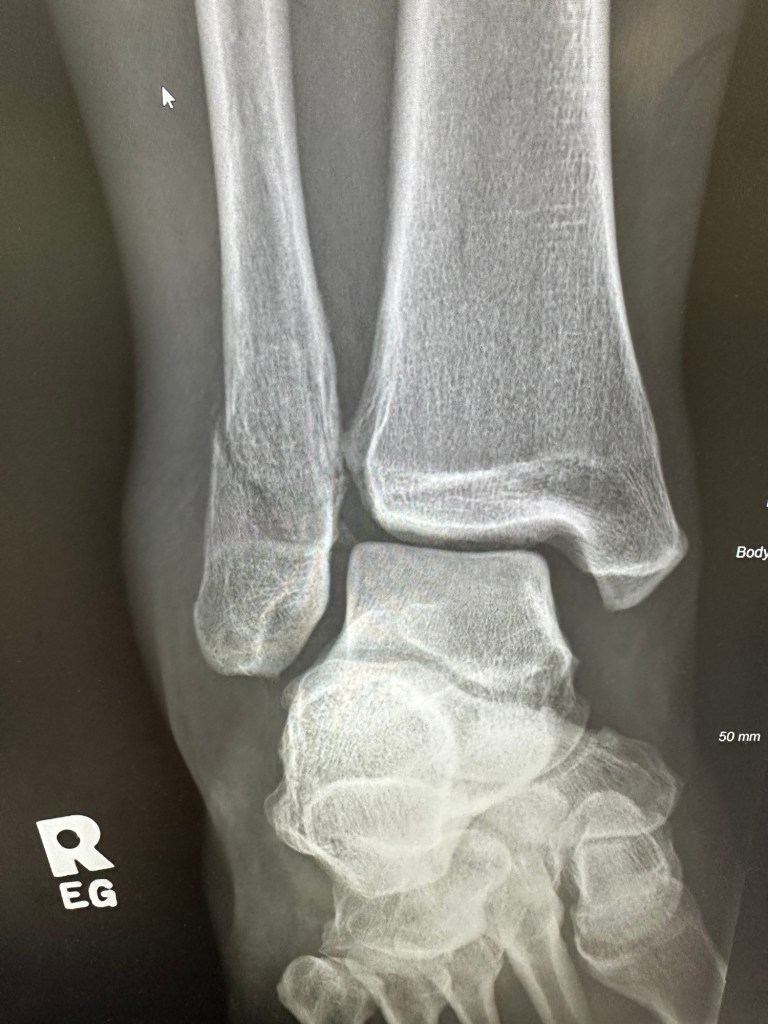

I had a pretty relaxed day, trying to rest the leg and get healing as needed. Sawyer and I played It Takes Two, Ash and I watched the last of Season one of A Man on the Inside, and I ran my last payroll of the year.